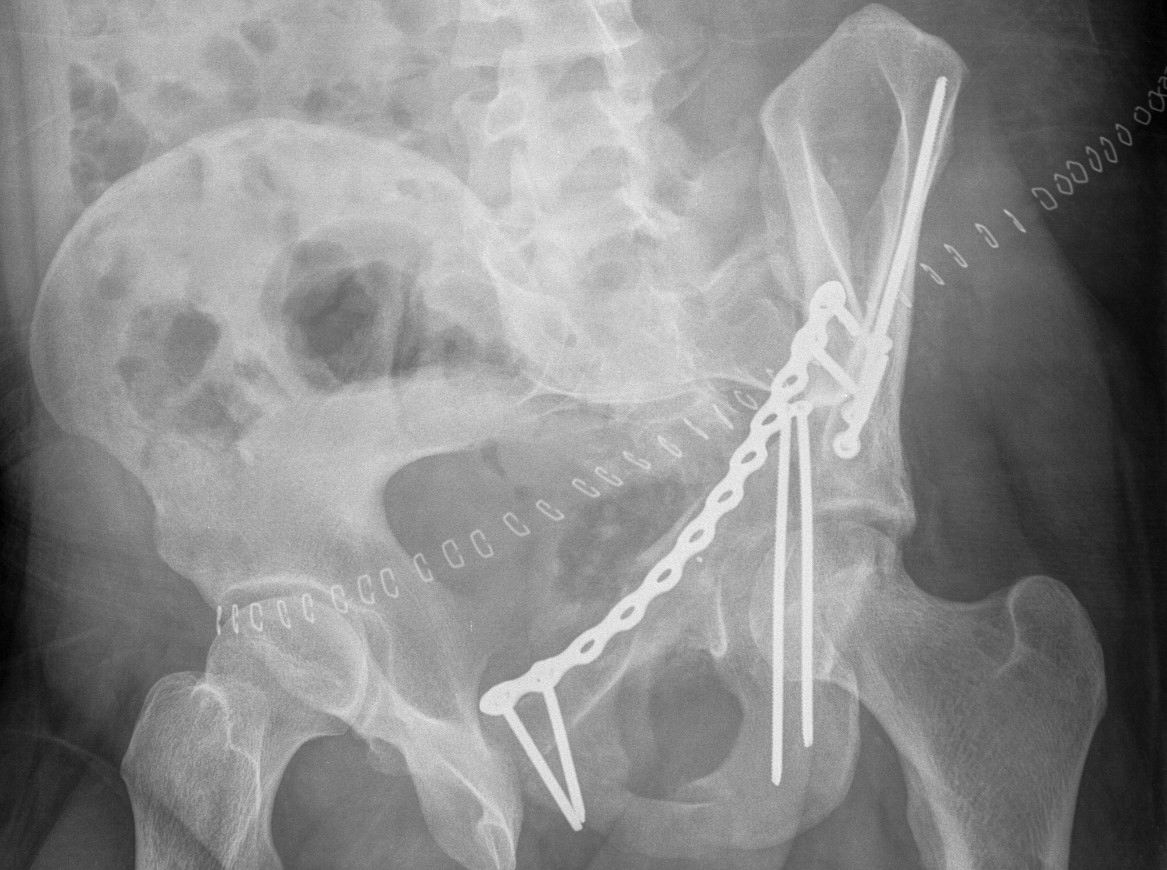

Anterior Column & Wall Fracture

ORIF

1. Reduce quadrilateral plate

- small T plate / will sit under pelvic reconstruction plate

- separate recon plate

2. Plate iliac crest fracture

- long 13 hole plate from pubis

- along superior pubic ramus up onto inner table of ilium

- indirect acetabular reduction